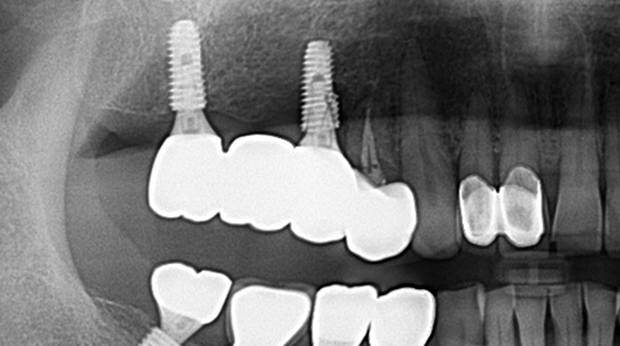

의식하진정법(수면마취)/임플란트

고난도 수술 진료

임플란트와 사랑니 발치는 외과적 시술로 잇몸을 절개하는 외과적 시술은

짧으면 짧을 수록 시술 후 붓기와 통증이 최소화됩니다.

치과의사 경력 14년차 구강외과 전문의가 빠르고 안전하게, 아프지 않게 수술해 드립니다.

치과경력 14년차 구강외과 전문의

연세대학교 치과대학 구강외과 임상 조교수